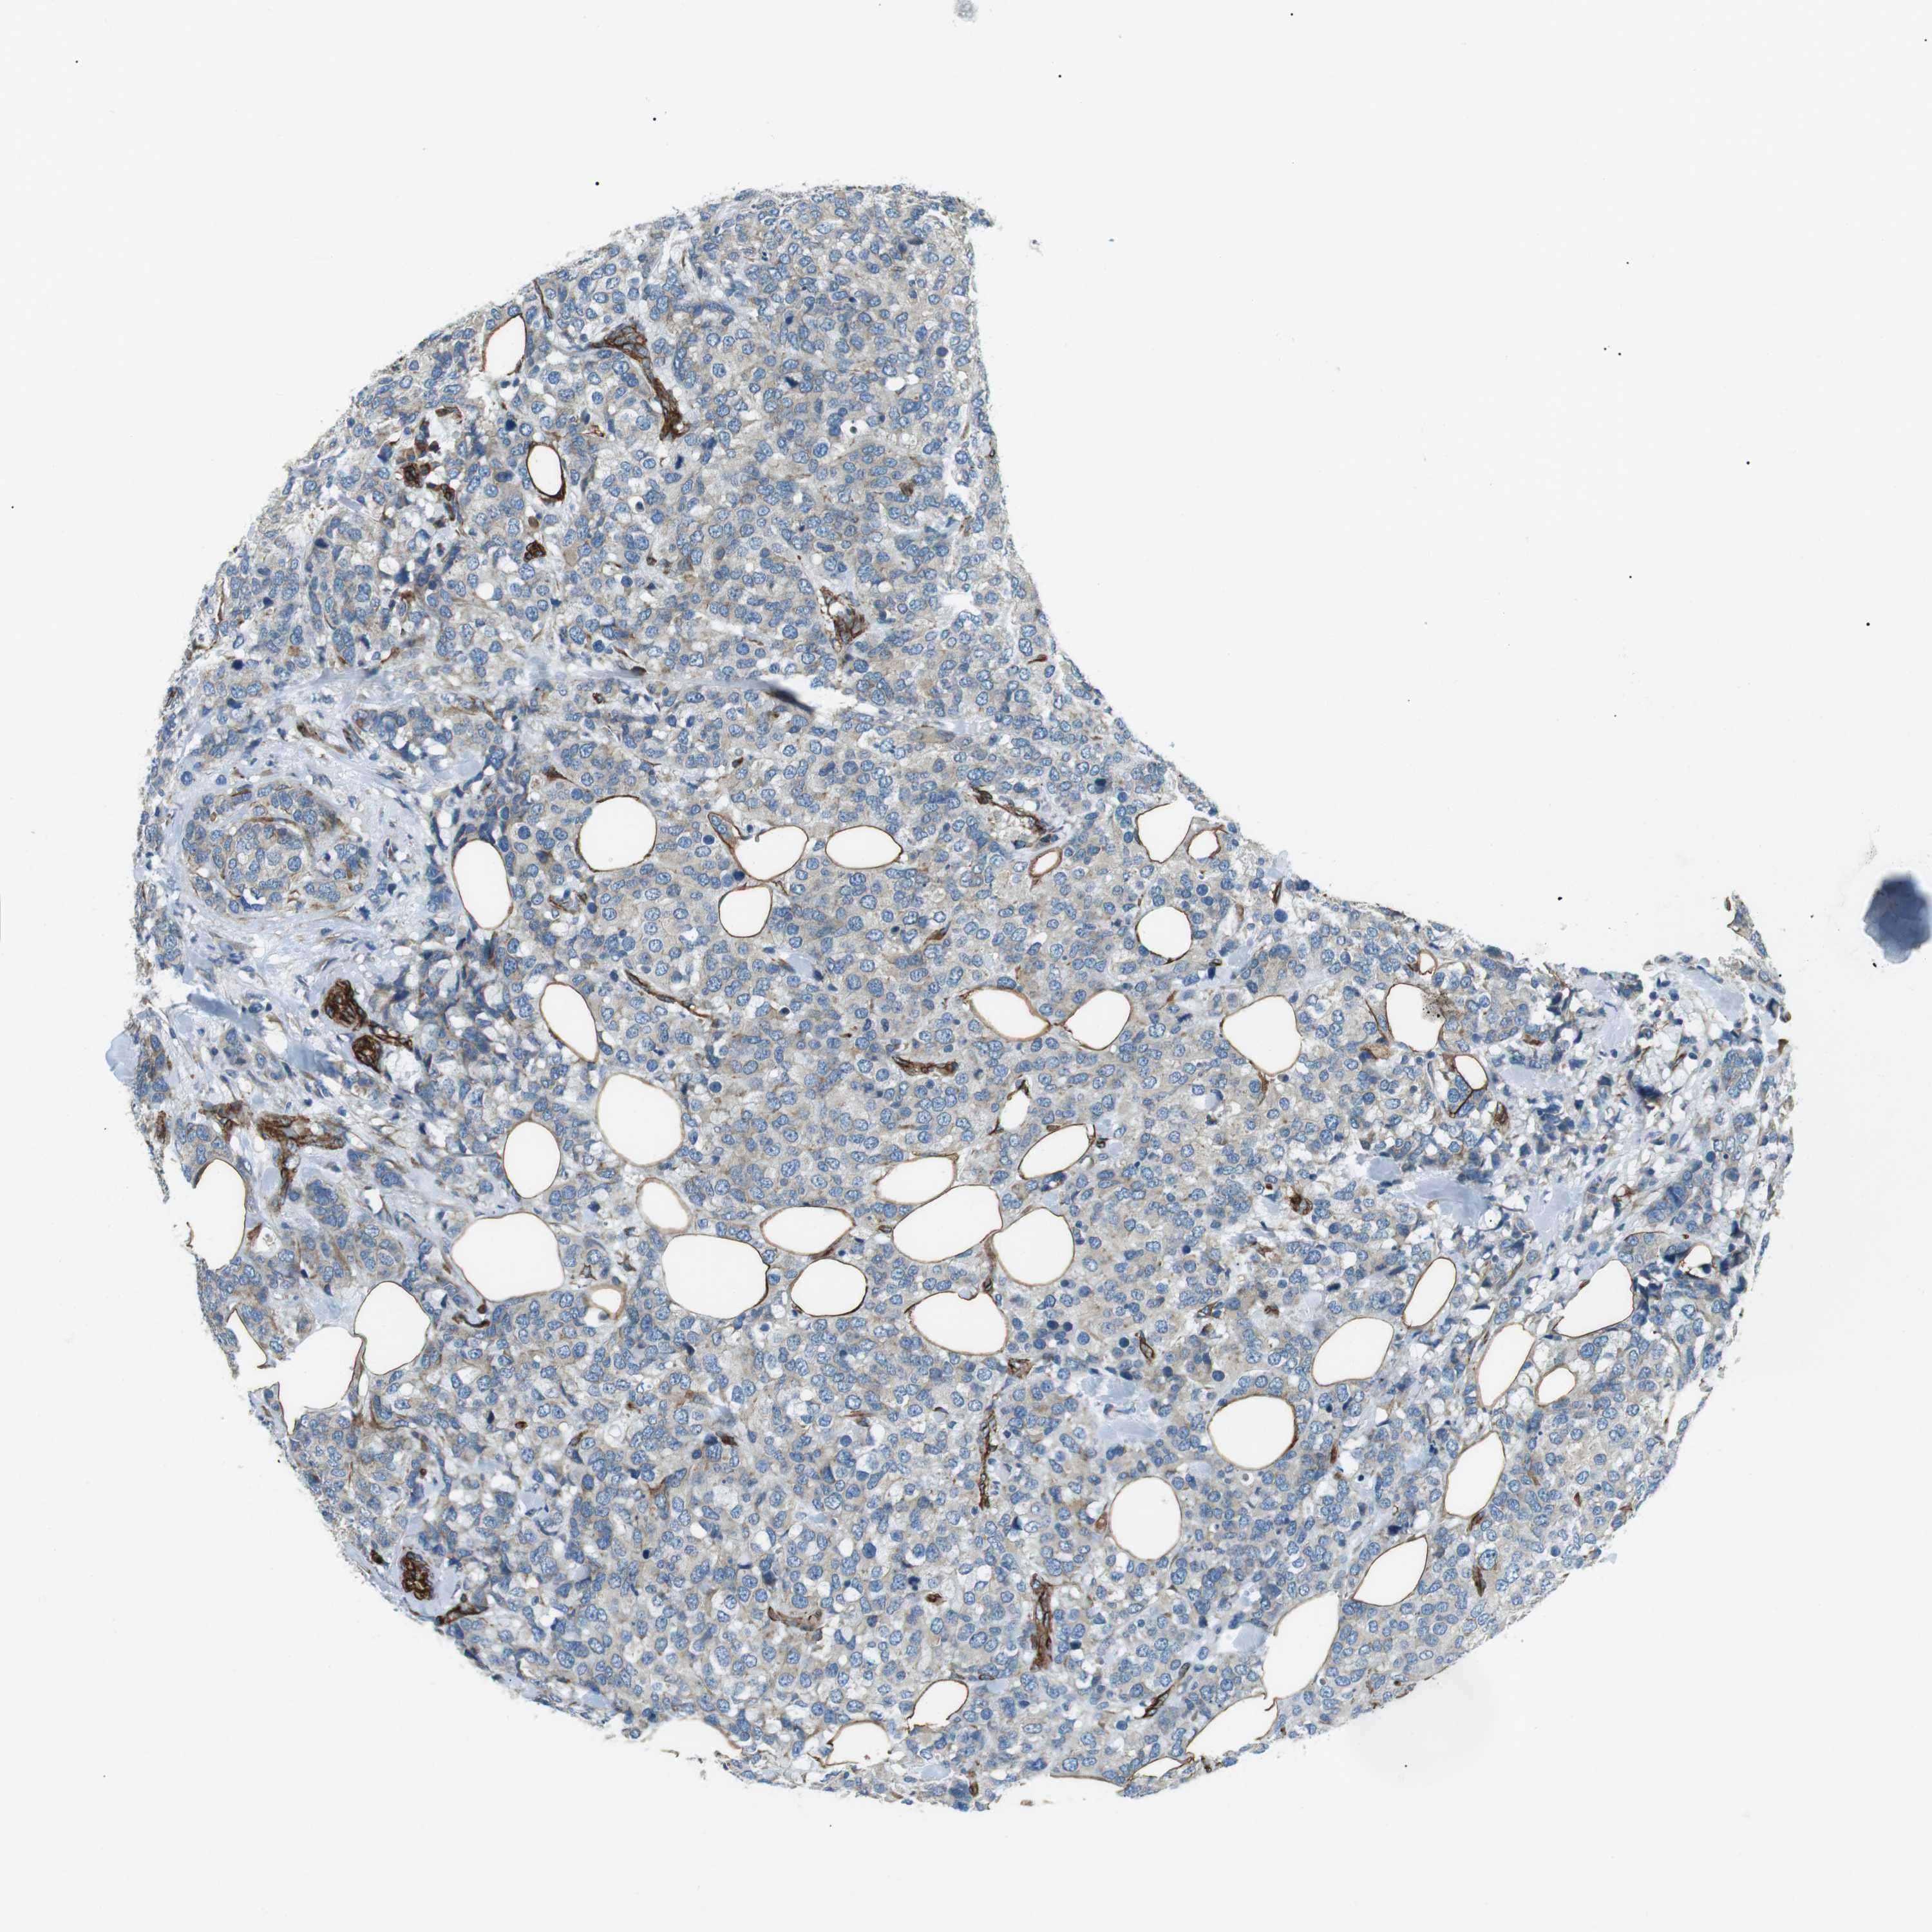

BRCA TCGA BRCA VALIDATION PROTEIN EXPRESSION

ANTIBODIES

AND

VALIDATION